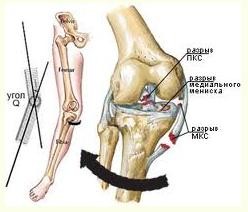

При вторичном артрозе дегенеративный процесс развивается уже в травмированном хряще. Причем, уже в начальной стадии процесса нередко биомеханические факторы в виде нарушения центрации, конгруентности суставных поверхностей и нестабильности сустава играют главенствующую роль. К вторичным артрозам коленного сустава приводит и болезнь Кенига. Развитие артроза после травм идет через воспаление, через артрит и синовит. В этих случаях для формирования артроза необходимо всего 4-5 месяцев. Вторичный гонартроз возникает под воздействием нескольких причин, таких как: воспаление (имеющее инфекционную или аутоиммунную природу), травма и дисплазия. Наиболее часто к гонартрозу приводят именно травматические повреждения коленного мениска - менископатии.

Различают следующие виды повреждений менисков:

• Отрыв мениска от места прикрепления в области переднего или заднего рога.

• Различные комбинации этих повреждений.

• Чрезмерная подвижность менисков (вследствие разрыва межменисковых связок или его дегенерации).

• Хроническая травматизация мениска.

• Кистозное перерождение мениска

В зависимости от характера повреждения мениска они бывают:

• Полные

• Неполные

• Продольные

• Поперечные

• Раздробленные

Повреждения латерального и медиального менисков имеют много общих черт. В то же время, для медиального мениска более характерными оказываются продольные и лоскутные разрывы, а для латерального - горизонтальные и поперечные разрывы.